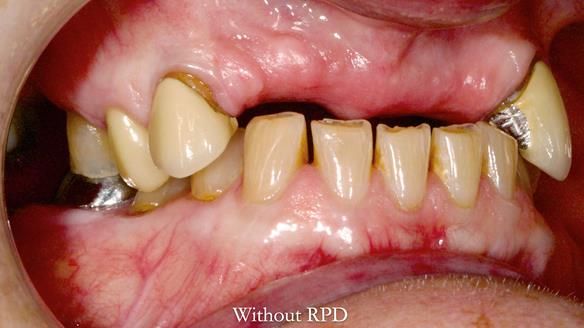

This is one of those cases that reminds me why I love removable prosthodontics. Pam was an absolute joy to treat — we were on the same page throughout. Her old upper flexible denture was loose, uncomfortable, and unaesthetic. We replaced it with a carefully designed metal-based upper partial denture/splint and new porcelain-bonded-to-zirconia (PBZ) crowns for the canines. The result is stable, comfortable, and natural-looking.

- Diagnosis and plan – Flexible upper denture ill-fitting with poor stability, retention, and appearance. Plan: metal-based upper partial denture/splint with lighter porcelain-bonded-to-zirconia crowns on UR3 and UL3.